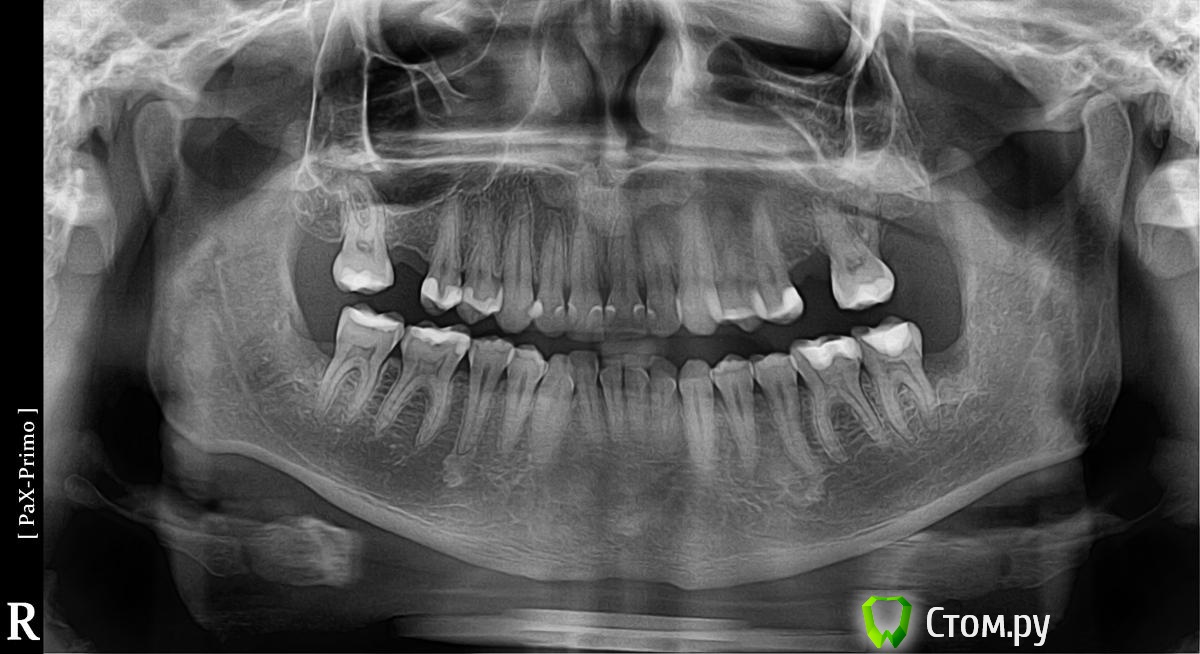

Serge1 Опубликовано 24 марта, 2014 Автор Поделиться Опубликовано 24 марта, 2014 (изменено) Вот панорамный снимок. Гайморит 2 раза пролечили не проходит, лор связывает проблему с зубами. Стоматологи говорят лечи гайморит зубы болят из за гайморита. Замкнутый круг. Завтра будут депульпировать и каналы пломбировать. В чем может быть проблема? говорят что боли и зуд в гайморовых пазухах с насморком может быть только если пломбированные каналы или там воспаление,но его там нет. Был в 6 больницах у 9 врачей стоматологов и был у 4 лоров. Я просто уже не знаю что и говорить или я бракованный или врачи упускают что то. Изменено 24 марта, 2014 пользователем Serge1 Ссылка на комментарий